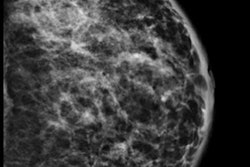

A 34-year-old woman with 50-mm suspicious palpable lump in the left breast. Top: Mammogram (lateromedial view, spot compression). It shows no mass, no architectural distortion, just three microcalcifications. Bottom: Sonogram shows no mass but a focal heterogeneity ("nonmass"). BI-RADS 4. Biopsy under ultrasound guidance: grade III ductal invasive carcinoma HER2+. All images courtesy of Dr. Martine Boisserie-Lacroix.